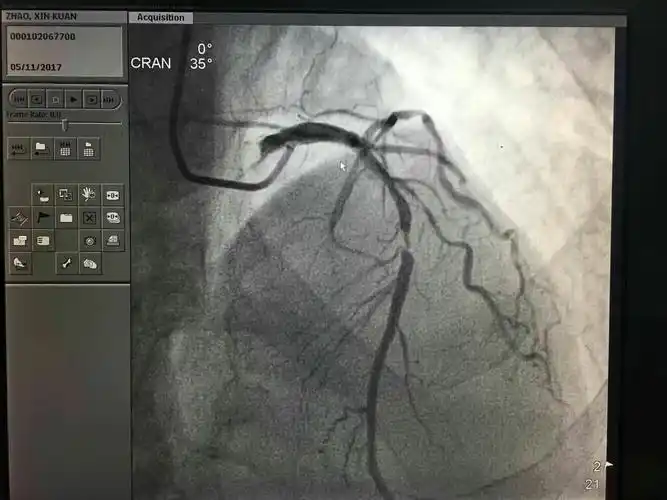

造影显示患者的冠状动脉回旋支近段完全闭塞.(翻拍照片)

术前,术后冠脉造影,血管从完全闭塞到血流畅通